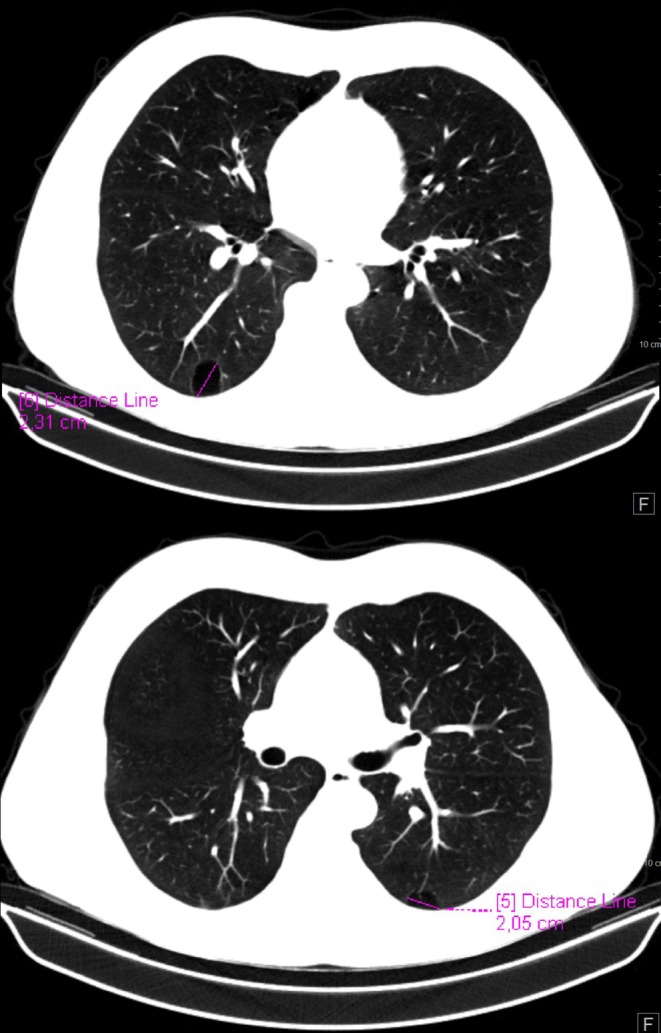

Still disease is a rare inflammatory disorder often triggered by infections or malignancies, with SARS-CoV-2 as a possible factor. This paper explores a 56-year-old patient who developed adult-onset Still disease after COVID-19. Symptoms included fever, arthralgia, rash, hepatomegaly, and joint swelling. Diagnosis followed Yamaguchi criteria and treatment with glucocorticoids and immunosuppressants led to recovery. The paper discusses similarities between Still disease and severe COVID-19 that suggest shared inflammatory mechanisms, particularly IL-1 activation. Early diagnosis and treatment are vital. Further research is needed to clarify the link between Still disease and SARS-CoV-2 and improve treatment strategies.